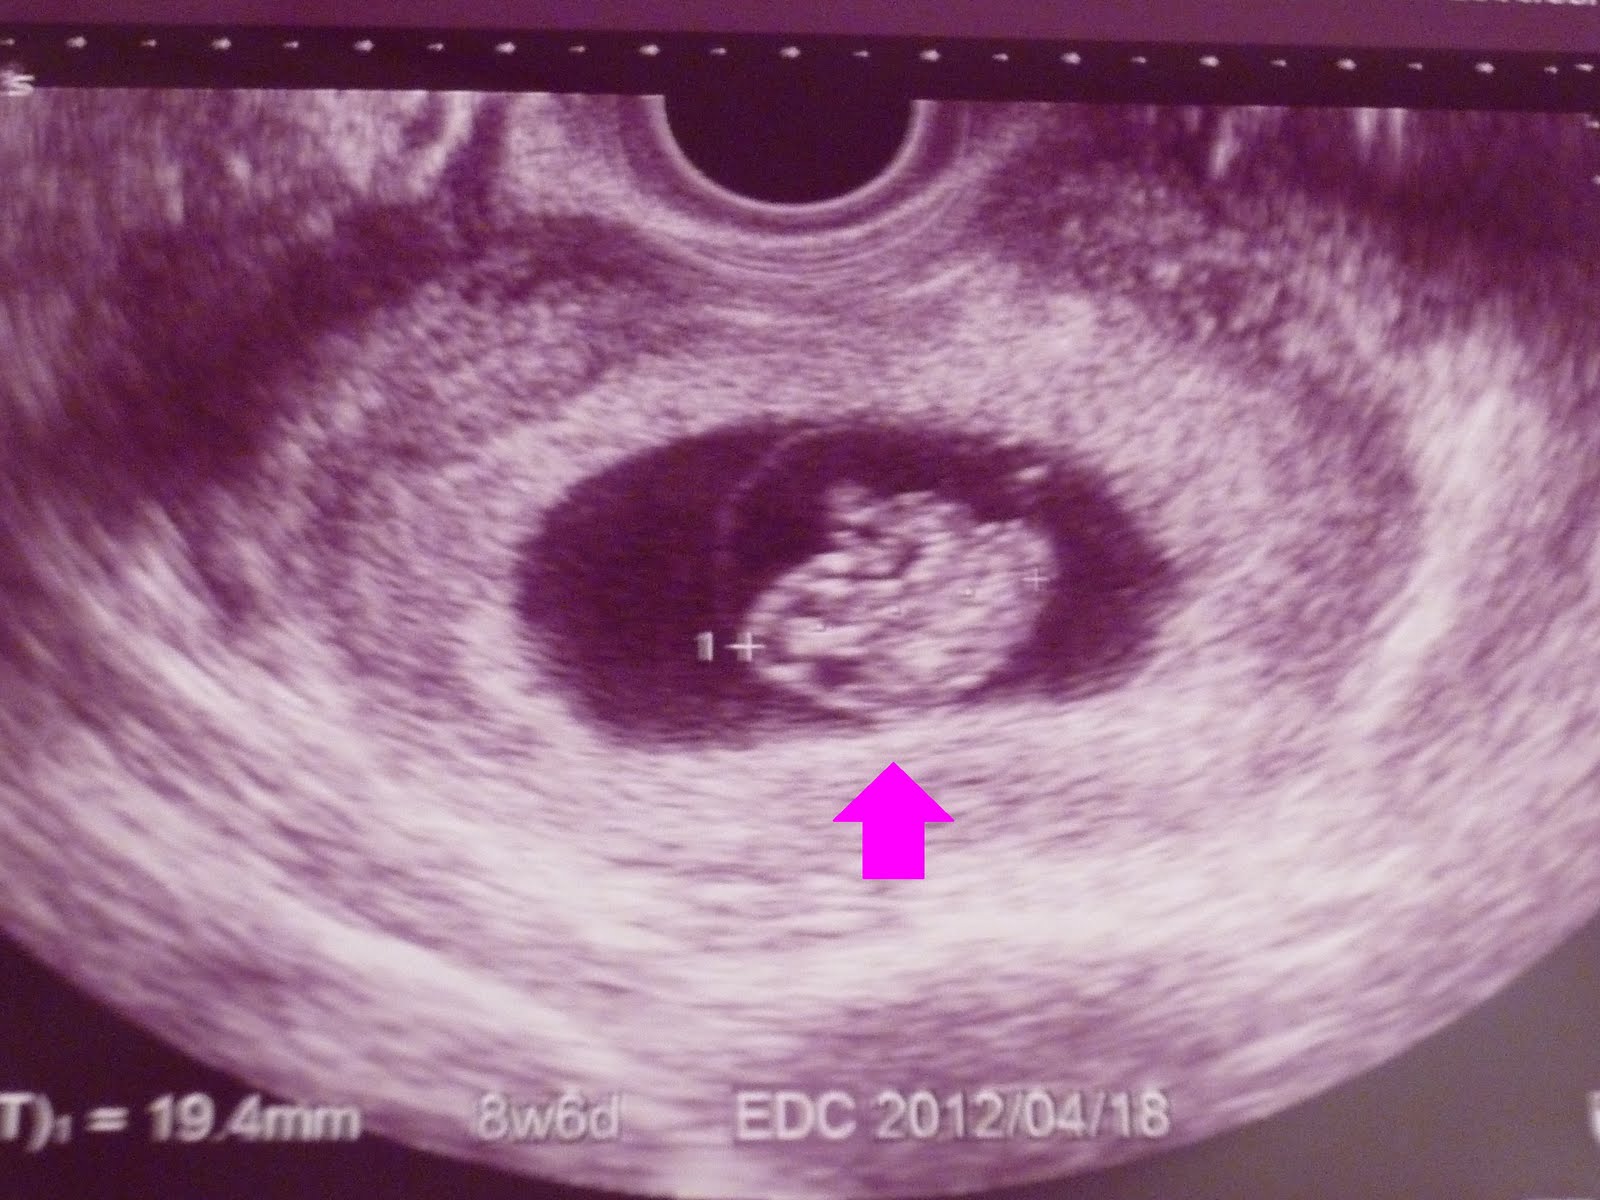

妊婦さんペースののんびりゆったりした旅行でした☆

さて、アワビの効果は出るか!?

目がキラキラした可愛い赤ちゃんが生まれますように!!!!